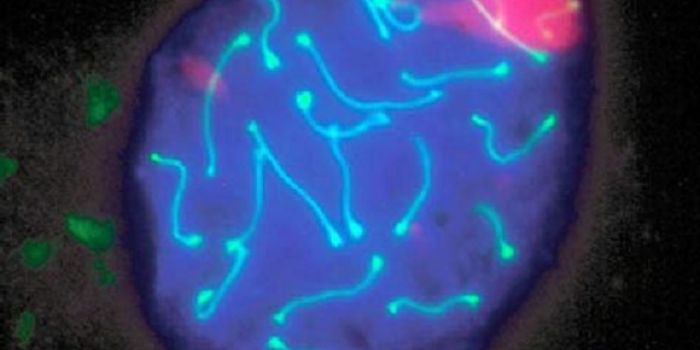

AUG 31, 2021Clinical & Molecular DXCellular stains are organic fluorescent dyes or fluorescent conjugates designed to localize to a specific organelle or c ...